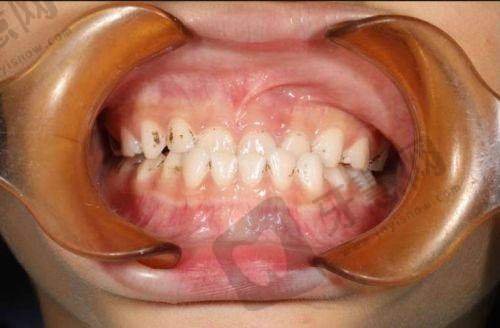

2. 口腔正畸科:开展传统固定矫正、隐形矫正、自锁托槽矫正等全品类正畸项目,特色技术为“数字化隐形矫正”和“儿童早期肌功能矫正”。时代天使冠军版隐形矫正采用3D打印牙模,每两周更换一副矫治器,矫正周期缩短至18 - 24个月;儿童MRC肌功能矫正通过趣味牙托训练不良口腔习惯,降低8 - 12岁儿童矫正难度。